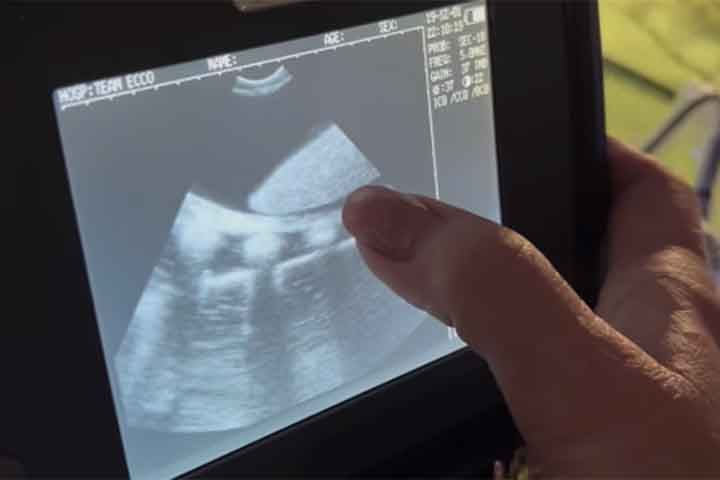

Arraia engravida sem contato com macho da espécie